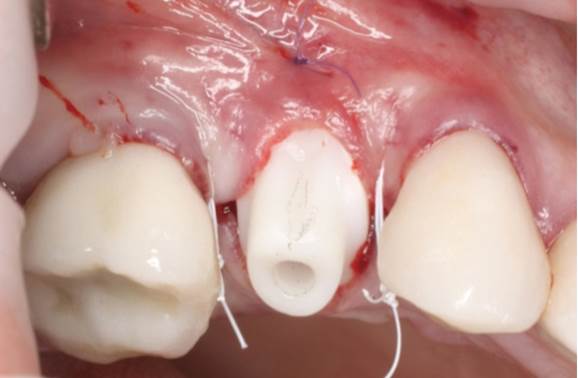

Clinical case: Extraction, immediate implant placement, & provisionalization

- Courtesy of Dr. Iulian Filipov, Romania -

AnyRidge, R2GATE, guided surgery, immediate placement, immediate provisionalization, initial stability, Dr. Iulian Filipov, #25, maxillary posterior, immediate loading, Mega ISQ

Products:

AnyRidge implant system, R2GATE, MEGA ISQ, Digital prosthesis